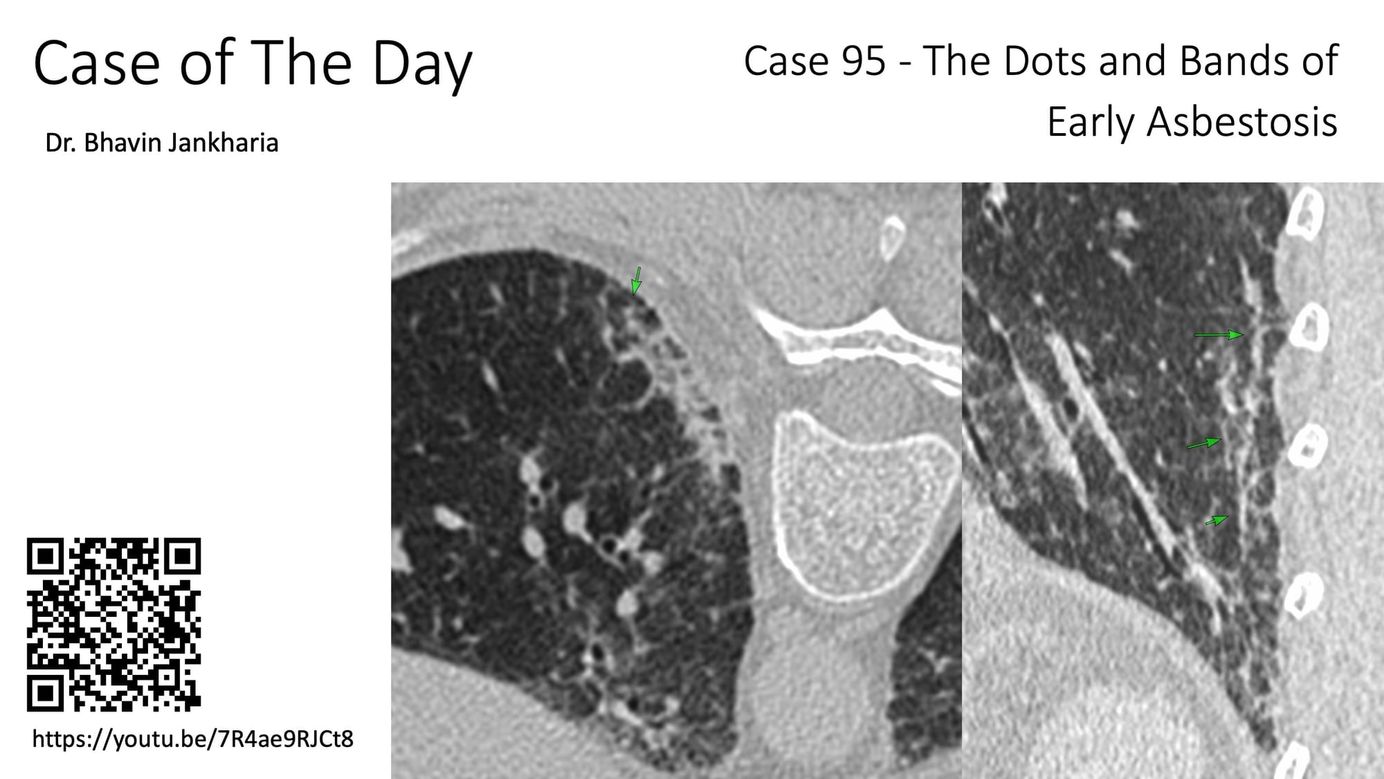

Case of the Day - 095 - 2025 09 03 - The Dots and Bands of Early Asbestosis Members Public

In patients with asbestos exposure, early asbestosis presents in a distinctive manner...however these signs do not help distinguish asbestosis from other ILDs if history of exposure is not known.